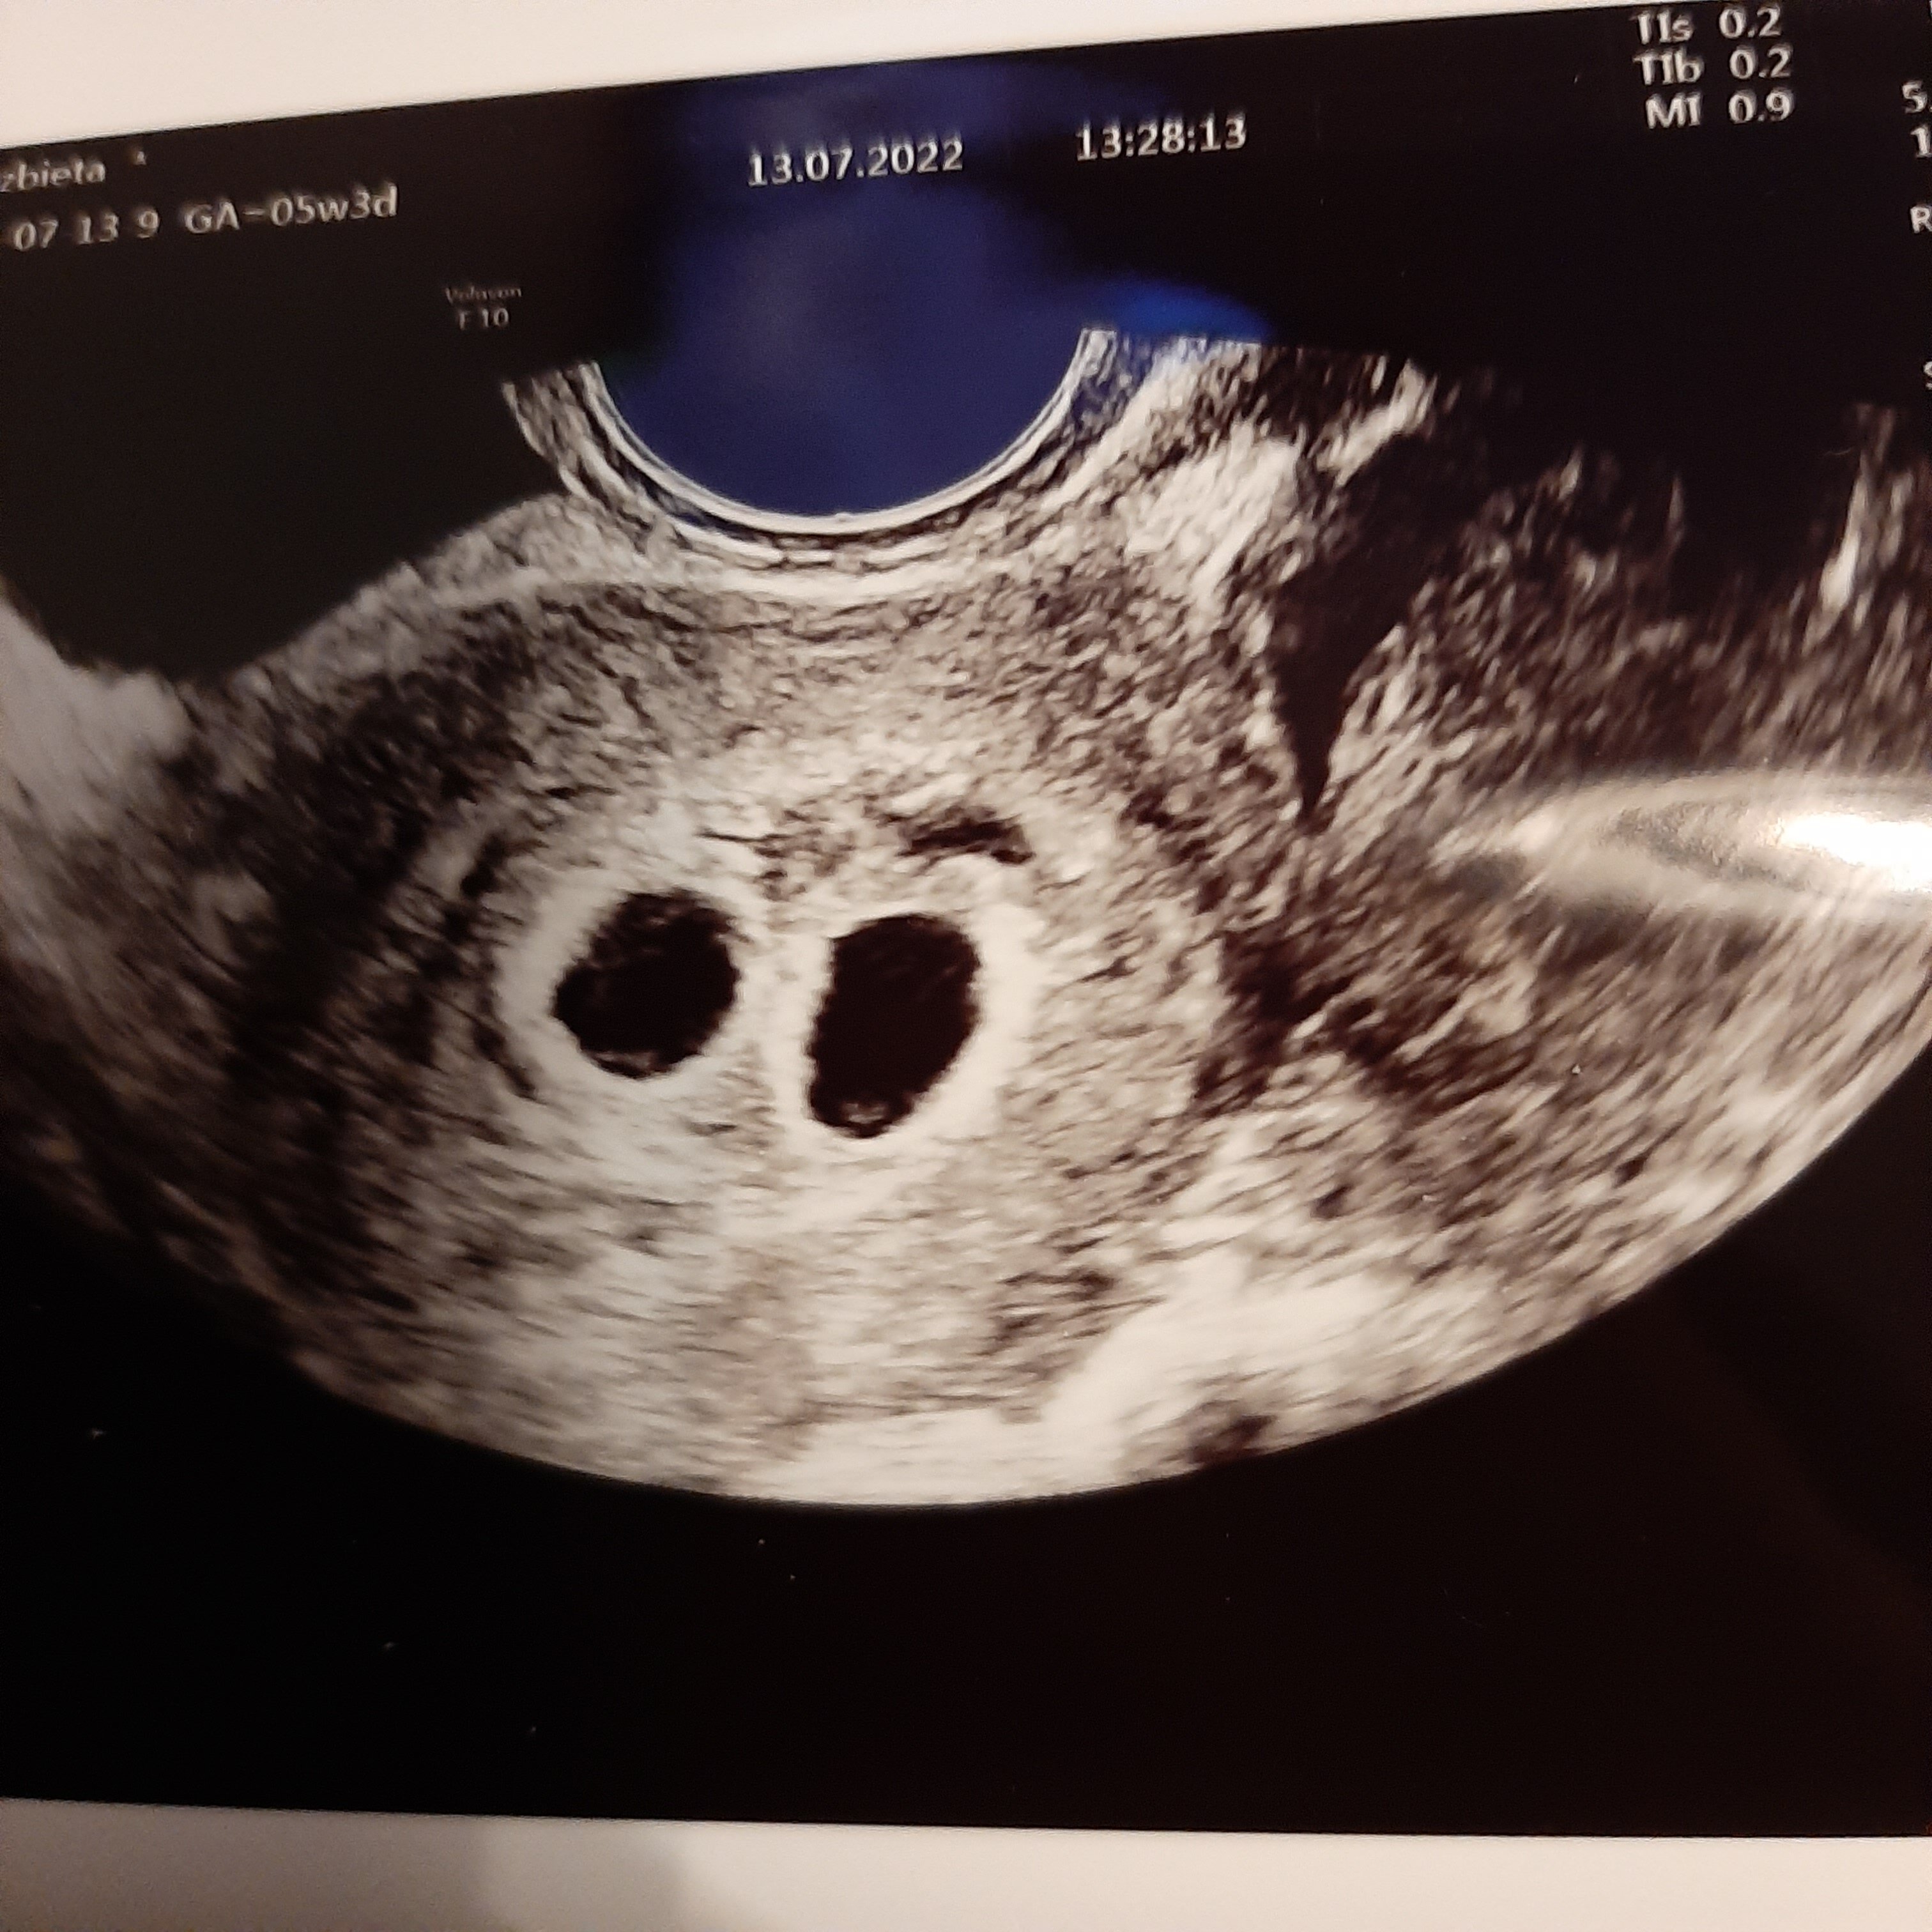

A to moje pierwsze usg z dwoma pęcherzykami![]()